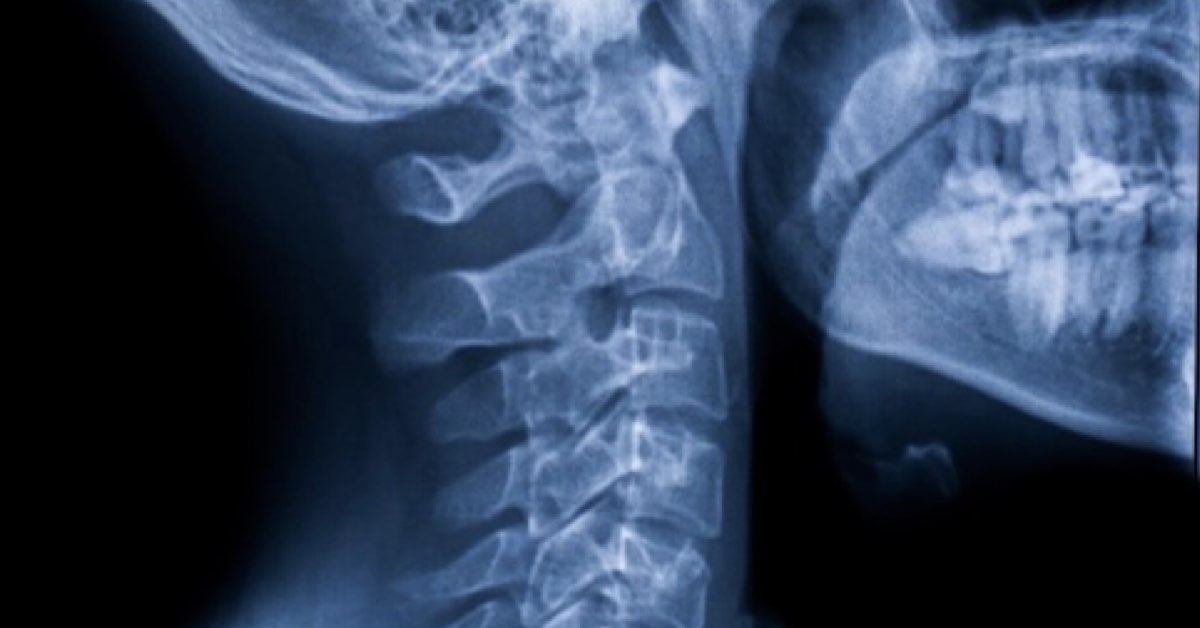

Acute neck pain is a common issue that can result from various factors, including muscle strains, poor posture, or injury. If you’re experiencing acute neck pain, physical therapy offers a comprehensive approach to relief and recovery. Here are key strategies that physical therapists use to manage acute neck pain effectively.

The first step in physical therapy is a thorough assessment. A physical therapist will evaluate your range of motion, strength, and specific areas of pain. Understanding the root cause of your neck pain is crucial for developing a personalized treatment plan.